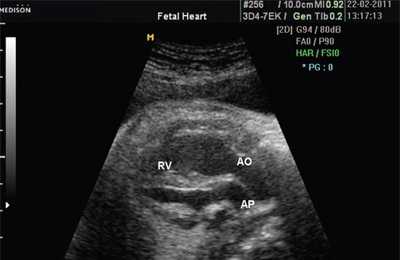

При эхокардиографии изучались четырехкамерный срез сердца плода (рис. 1) и срез через три сосуда (рис. 2). УЗИ проводилось трансабдоминальным датчиком, лишь при необходимости (затрудненная визуализация) использовался внутриполостной датчик. Четырехкамерный срез сердца плода при ультразвуковом сканировании трансабдоминальным датчиком визуализировался в 85% случаев, срез через сосуды - в 73%, при использовании трансвагинального датчика эти цифры существенно возрастали до 100 и 91% соответственно. Оптимизация пренатальной диагностики ВПС может быть достигнута путем строгого соблюдения основных методических правил. При оценке четырехкамерного среза плода необходимо оценить нормальное расположение сердца плода, исключив его эктопию (рис. 3), положение оси сердца плода, что не представляет никаких трудностей, нормальные пропорции и размеры камер сердца, движение створок атриовентрикулярных клапанов должно быть свободным, септальная створка трикуспидального клапана должна располагаться ближе к верхушке сердца (рис. 4). При оценке среза через три сосуда необходимо оценить взаиморасположение сосудов и их диаметр.

Рис. 1. Беременность 12 недель. Четырехкамерный срез сердца плода. Отчетливо видны камеры сердца.

В равной степени это относится к дефекту межжелудочковой перегородки (рис. 6), простой форме транспозиции магистральных сосудов (рис. 7, 8), транспозиции магистральных сосудов с дефектом межжелудочковой перегородки (синдром Тауссиг - Бинга) (рис. 9), общему желудочку (рис. 10), общему артериальному стволу (рис. 10), двойному отхождению сосудов от одного из желудочков сердца (рис. 11).

LV и RV - левый и правый желудочек, АР - легочная артерия, АО - аорта, VSD - дефект межжелудочковой перегородки.